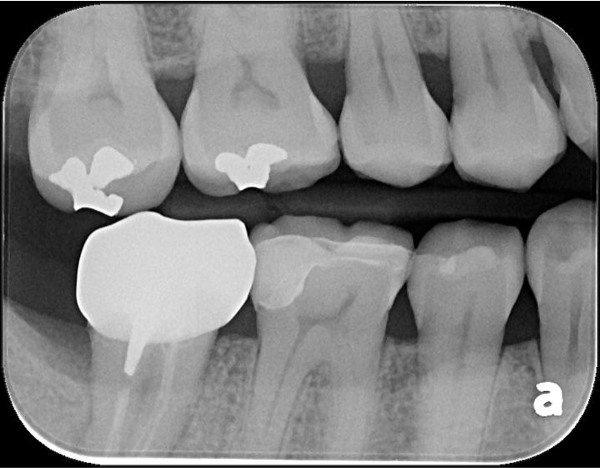

治療前,二次蛀牙,咬頭受損

蛀牙未到牙髓

當蛀牙破壞程度大

陶瓷冠塊體是根據蛀牙的窩洞量身訂做,不管是顏色、精密度都是最佳的選擇,因此是非常美觀與持久的填補窩洞材料與技術